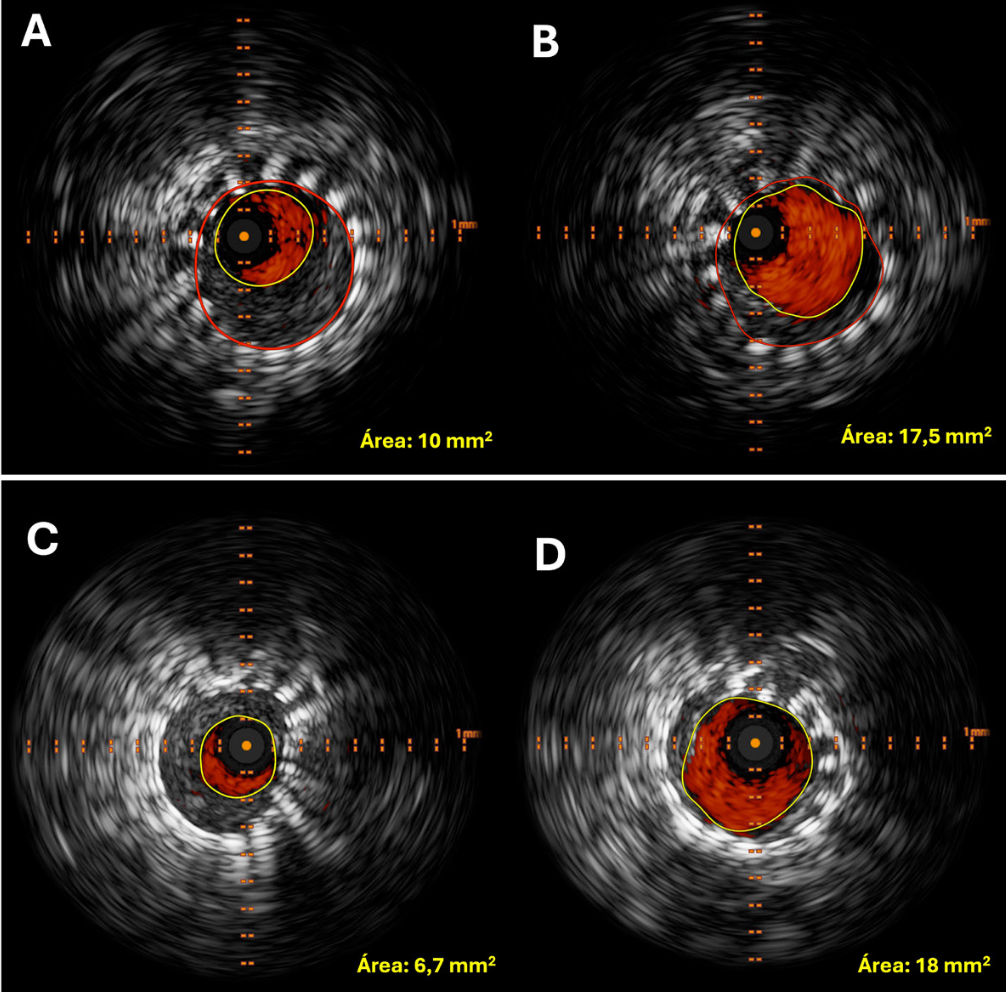

Imágenes y Cirugía

|

Diego Soto V, Cristian Marín O, Sebastián Morales Z